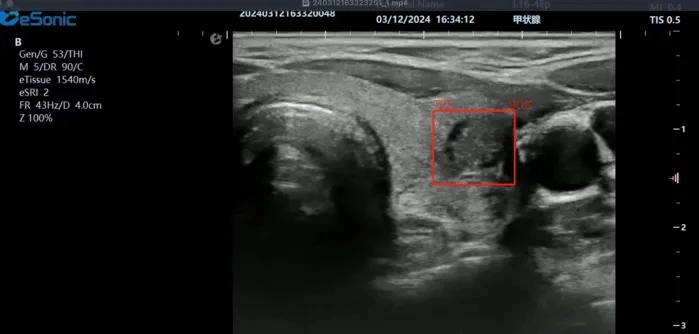

银河官网医疗(ESI)表示,其最新的人工智能功能可以帮助到医疗机构的工作效率,功能包括,实时、动态、快速自动识别病灶,良恶性病灶概率预测,甲状腺结节和乳腺的二维灰阶动态自动实时检测需求,提供多个结节动态检测轮廓框。实时获取多幅具备临床特征(大小、属性等)的结节切面,同时提供当前切面所示结节的结节大小、属性特征、TI-RADS 分级。

对于甲状腺结节相关的自动检测功能,甲状腺结节病灶检出率≥95%,良恶性分类灵敏度≥90%、良恶性分类特异度≥85%。